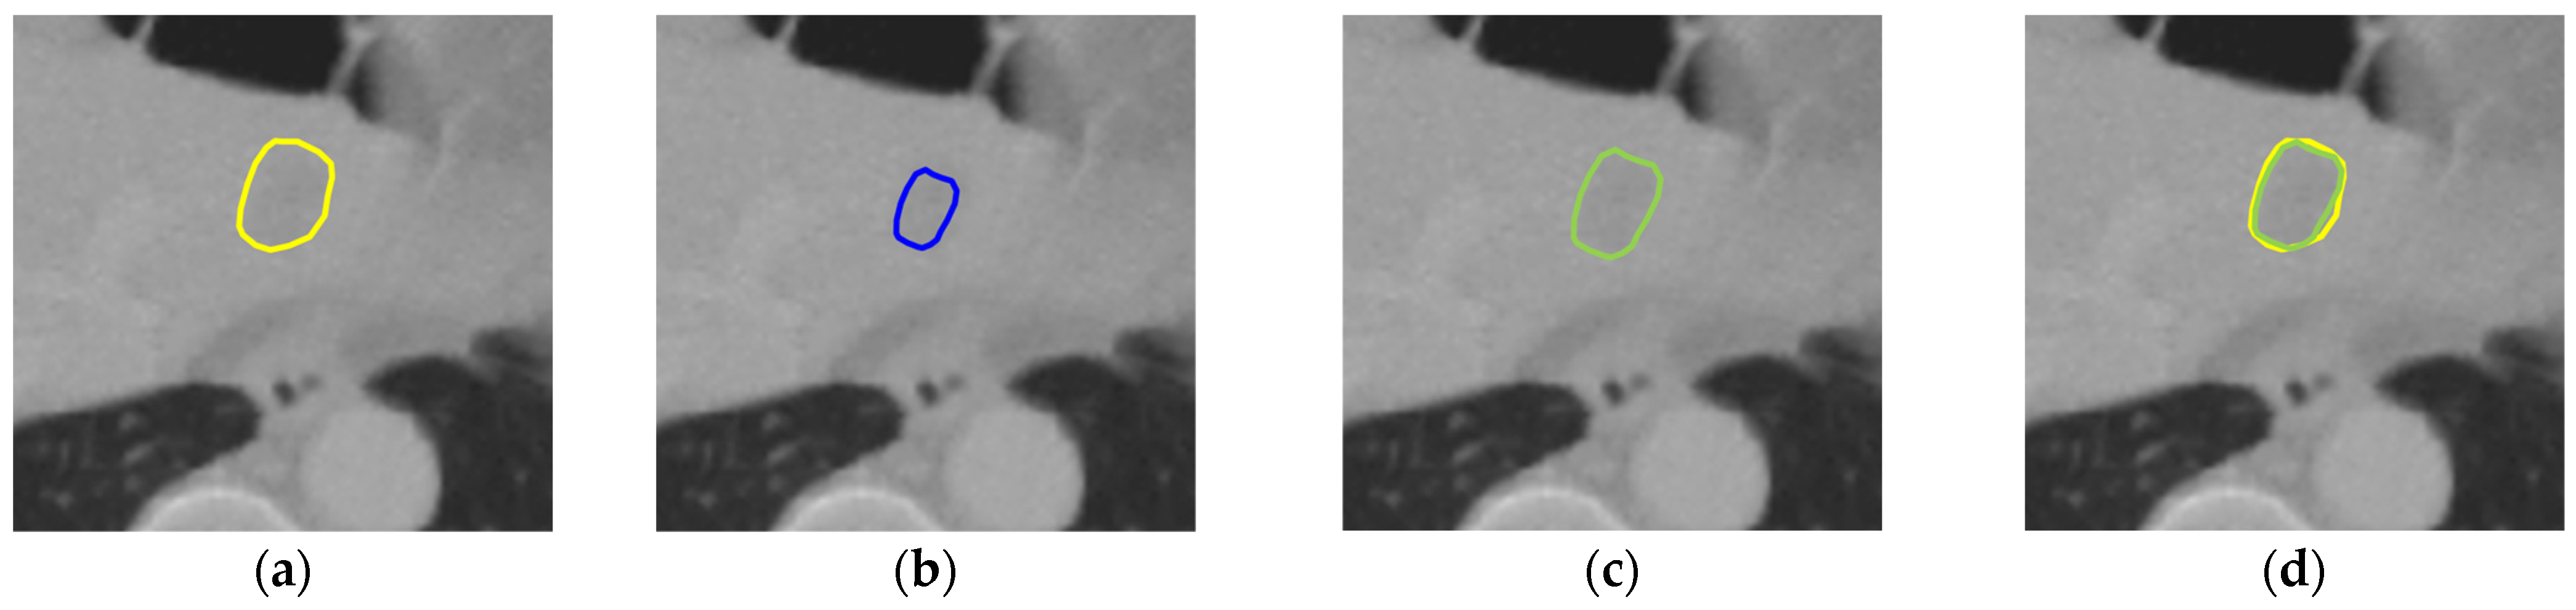

Nevertheless, our study has limitations in certain aspects. The introduction of the two gradient-enhanced encoders increases the complexity level of our model and therefore the computational cost. Furthermore, the tumor segmentation performance can be affected by the liver segmentation performance. The proposed method achieved high performance on both the LiTS dataset and the 3DIRCADb dataset, with an average DSC of 97.38% and 97.50% for liver segmentation, respectively. However, in some cases, tumors may be missing in the segmented liver region, as shown in Figure 9c. Then, in the masking step, those tumors will be excluded from the CT images masked by the extracted liver region, which will be used as the input for tumor segmentation. In that case, those tumors will be missing in tumor segmentation, as shown in Figure 9d. In addition, our model may occasionally miss segmenting some extremely small tumors, as shown in Figure 10. This could be caused by tumor size imbalance and biased annotation for small lesions in the public datasets used for our model development. For our future work, the proposed two-step liver tumor segmentation pipeline can be reduced to a single-step pipeline by applying an end-to-end framework. This would enable a direct extraction of tumors from the original CT scans, thereby reducing computational costs and potentially enhancing the robustness of the segmentation process. Furthermore, the sizes of the datasets used for model training and evaluation are relatively small. To strengthen the experimental validity, the performance of the proposed model needs to be further evaluated using k-fold cross-validation or a larger dataset. Lastly, the ablation study is limited in scope and primarily focuses on the effect of post-processing. Though the ablation study in our previous work [19] concluded that the inclusion of the proposed gradient-enhanced encoders and a hybrid loss function that incorporates the HD loss are effective in improving the performance of liver segmentation, their effects on liver tumor segmentation were not studied in the current study. For future work, a comprehensive ablation study that analyzes the impacts of the gradient-enhanced encoders, the proposed hybrid loss function, and the EPA blocks on improving liver tumor segmentation performance will be conducted.

Figure 10. An extremely small tumor missing in the final tumor segmentation results: (a) the original CT slice; (b) the ground truth for the liver (red) and tumors (orange) with an extremely small tumor (highlighted in a dotted circle); (c) the liver segmentation result; (d) the tumor segmentation result (orange) with one tumor missing (highlighted in a dotted circle).